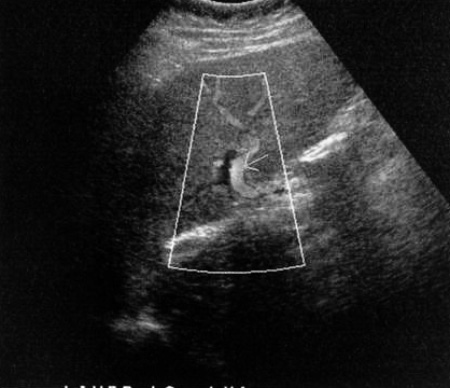

В воротной вене гепатопедальный кровоток (направлен в сторону печени) демонстрирует монотонную постоянную форму. На цветовой допплерографии сигнал заполняет всю площадь просвета сосуда, что дает основание исключить тромбоз воротной вены (может быть анэхогенным). Спектральная допплерография демонстрирует низкую скорость потока (15-40 см/с), который может быть двунаправленным в результате завихрений, возникающих в крупных венах с медленным кровотоком. Гепатофугальный (обратный) кровоток по воротным венам определяется при портальной гипертензии, если портосистемные анастомозы хорошо функционируют (фото 2).

Фото 2. Воротная вена печени в норме. А – цветовая допплерограмма правой ветви воротной вены: определяется гепатопедальный кровоток. В – пульсовая кривая воротной вены в норме